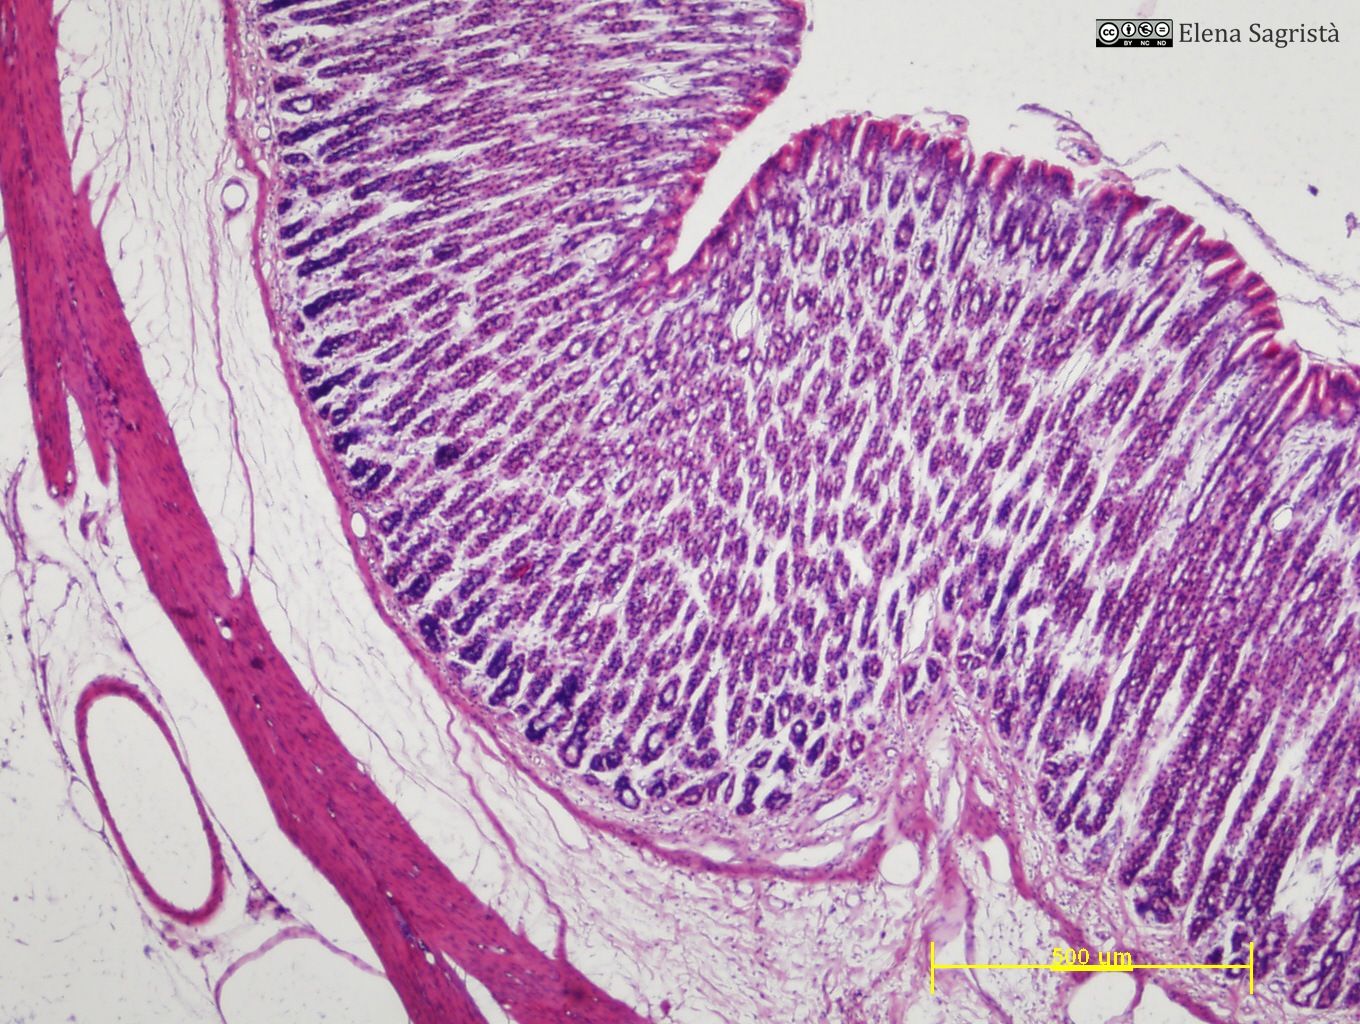

Histologia imatges: 16 Estòmac

Imatges de preparacions histològiques d'Estómac. Microscopia òptica.